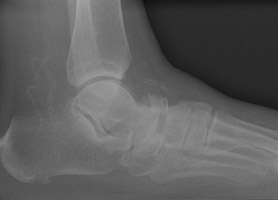

- Click on the image for a larger versionALateral radiograph of the foot. There is a mildly displaced fracture of the navicular.